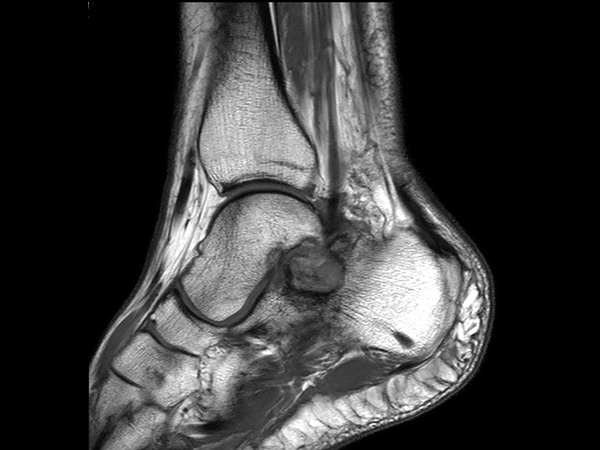

Sagittal T2w SPAIR